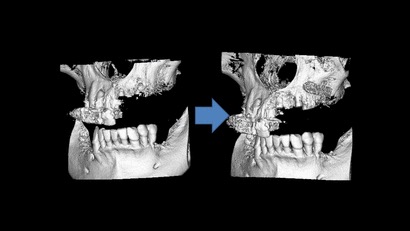

サイナスリフトにより上顎洞の横から

骨に穴を開け骨造成を行った症例

インプラント1本埋入のケースでも事前にCTシミュレーションを行い、副鼻空との関係や、下顎臼歯部なら下顎管との距離や補綴する歯との位置関係を把握します。

シビアなケースでは1本でもサージガイドを作製するなど安心安全なインプラント治療を行っています。